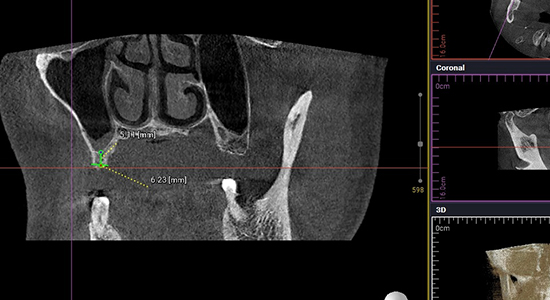

임플란트 시술을 위한 정밀진단

치아를 빼고 오래 방치하거나 치아를 잡고 있는 치조골이 많이 녹은상태에서 치아를 빼면 위쪽 턱뼈가 부족할 수 있습니다.